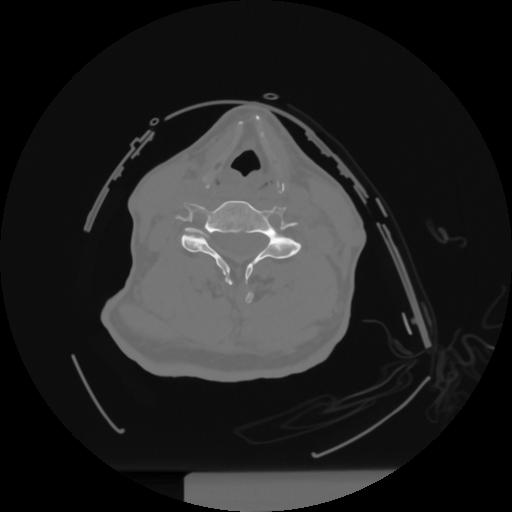

12 P.BLANDAS,,Vol,0.5,P.BLANDAS,,